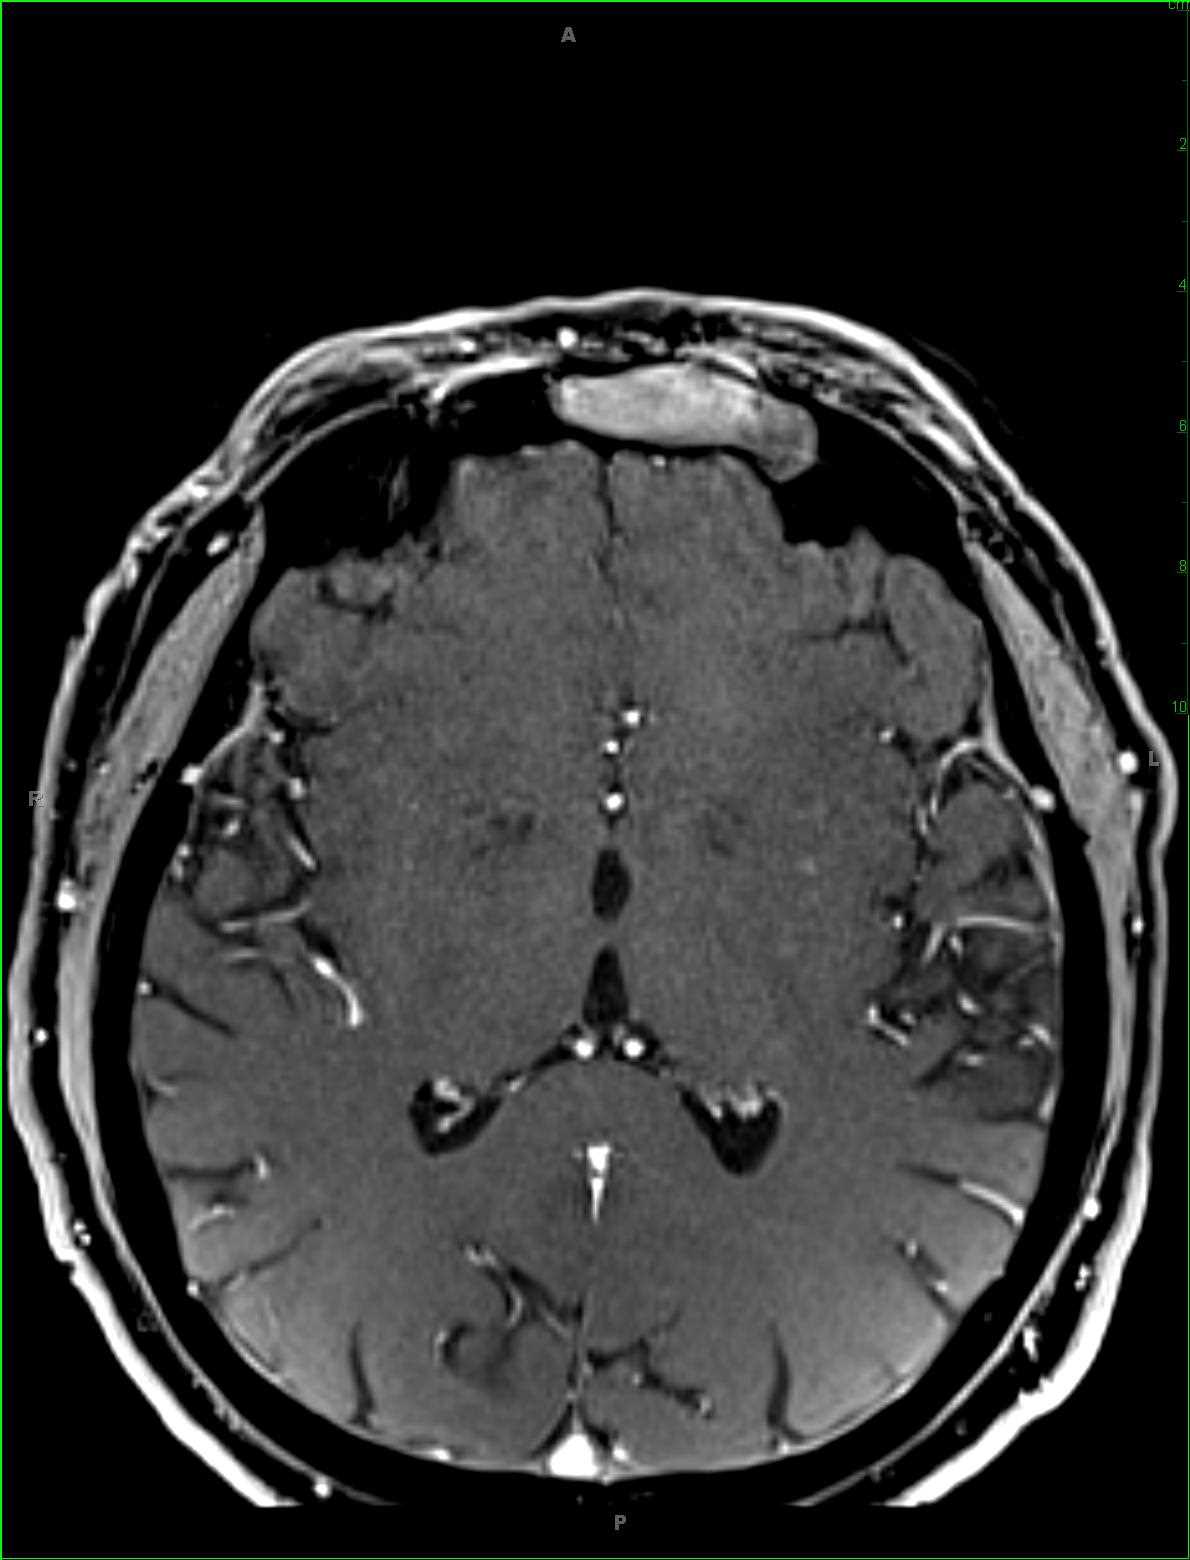

This is a case of leptomeningitis secondary to listerioris in a 62-year-old female. The first and second images, pre- and postcontrast sagittal T1-weighted sequences, demonstrate diffuse leptomeningeal thickening and enhancement in the cervical, thoracic, and lumbar spinal regions. These findings are confirmed on the axial cervical and thoracic spinal sections, images 3 and 4. Within the lumbar spine, there is not only thickening and enhancement of the leptomeninges but also evidence of acrachnoiditis with thickening, clumping, and distortion/tethering of the cauda equina. The inflammatory reaction to the bacterial pathogens results in tight junction opening of the endothelial cells, allowing the pathogens access to the leptomeningeal surfaces. The differential diagnosis for diffuse leptomeningeal enhancement includes infection, subarachnoid hemorrhage, metastases, granulomatous inflammation and infarction.